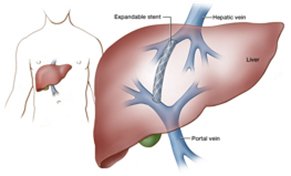

- A transjugular intrahepatic portosystemic shunt (TIPS) is a percutaneously created connection within the liver between the portal and systemic circulations.

- It is placed to reduce portal pressure in patients with complications related to portal hypertension.

- The goal of TIPS placement is to divert portal blood flow into the hepatic vein, so as to reduce the pressure gradient between portal and systemic circulations.

- Shunt patency is maintained by placing an expandable metal stent across the intrahepatic tract